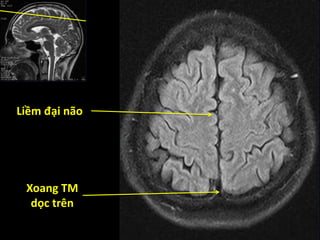

Liềm đại não

Xoang TM

dọc trên

Não thất bên

Thùy chẩm

Đám rối mạch mạc